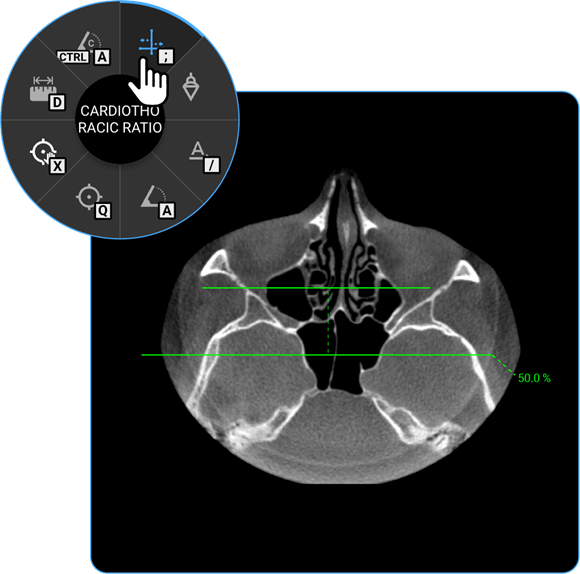

1. Cardiothoracic Ratio: Click on the Cardiothoracic Ratio tool to calculate the ratio of the cardiac width to the thoracic width on chest radiographs, aiding in the evaluation of heart size.

vai